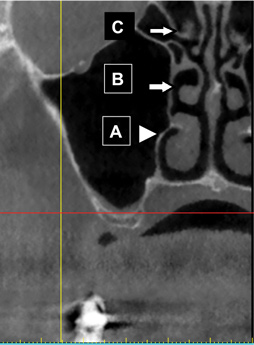

Fig 24. Turbinate bones: cross-sectional view. They are found within the nose. There is an inferior (A), middle (B), and superior turbinate (C).

Figure 24